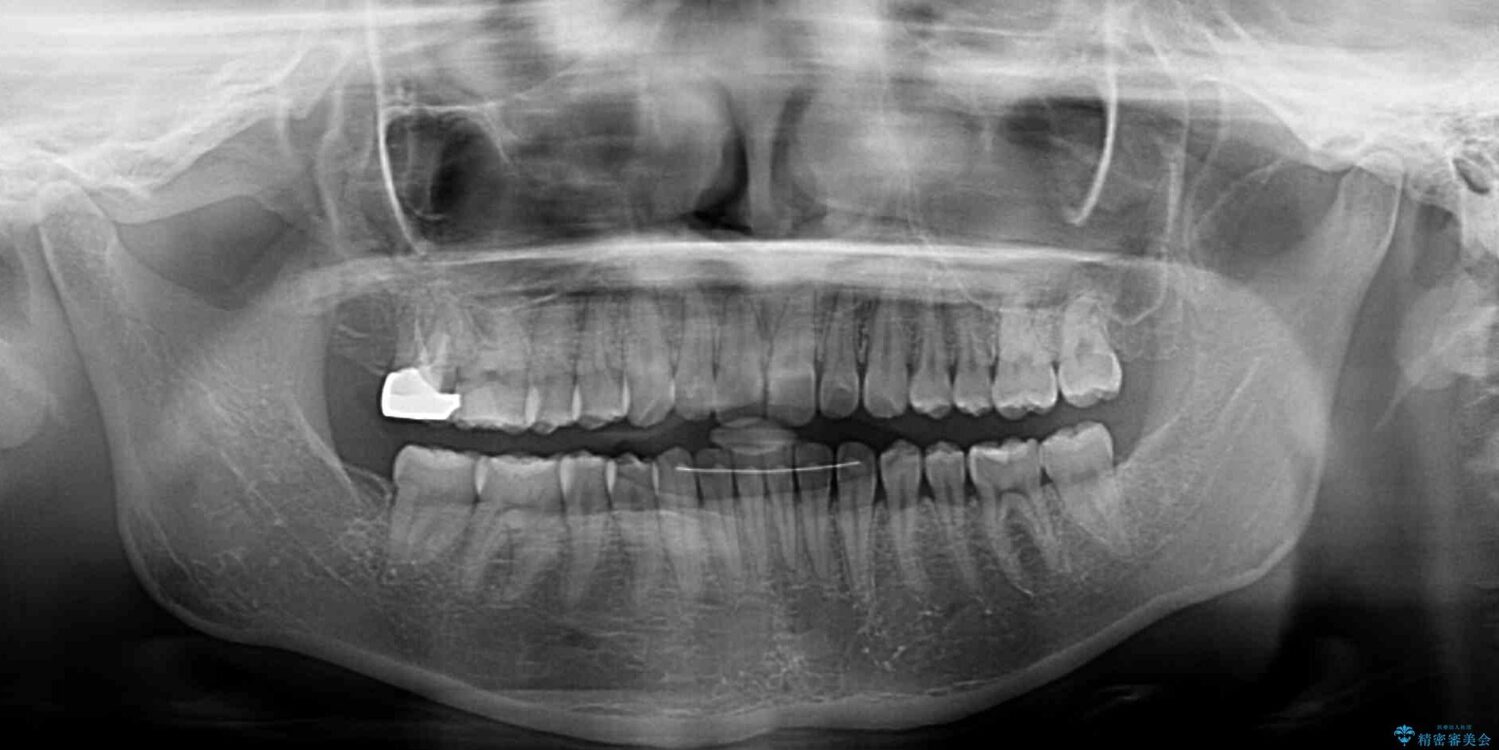

治療前、下顎前歯のデコボコが集中しており、奥歯の咬み合わせは、上顎に対して下顎が前方位にある状態でした。下顎の歯列を後方へ移動させる治療はインビザラインの得意とするところですので、1年程度で無事に治療を終えることができました。

治療途中

• 【モニター】下顎前歯のデコボコをインビザラインできれいに 治療途中画像